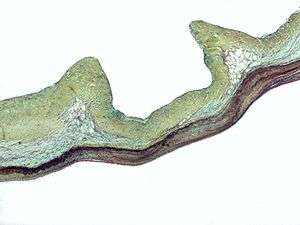

Aortic valve replacement is a surgical procedure in which a patient's aortic valve is replaced by a different valve. The aortic valve can be affected by a range of diseases and require aortic valve replacement. The valve can become either leaky (regurgitant or insufficient) or stuck partially shut (stenotic). Aortic valve replacement traditionally required open heart surgery. A new alternative is transcatheter aortic valve replacement (TAVR), which delivers a mechanical valve to the site of the diseased valve through a catheter.[5] There are two basic types of artificial heart valve, mechanical valves and tissue valves. Tissue heart valves are usually made from animal tissues, either animal heart valve tissue or animal pericardial tissue. The tissue is pretreated by removing antigens to prevent rejection and to prevent calcification.